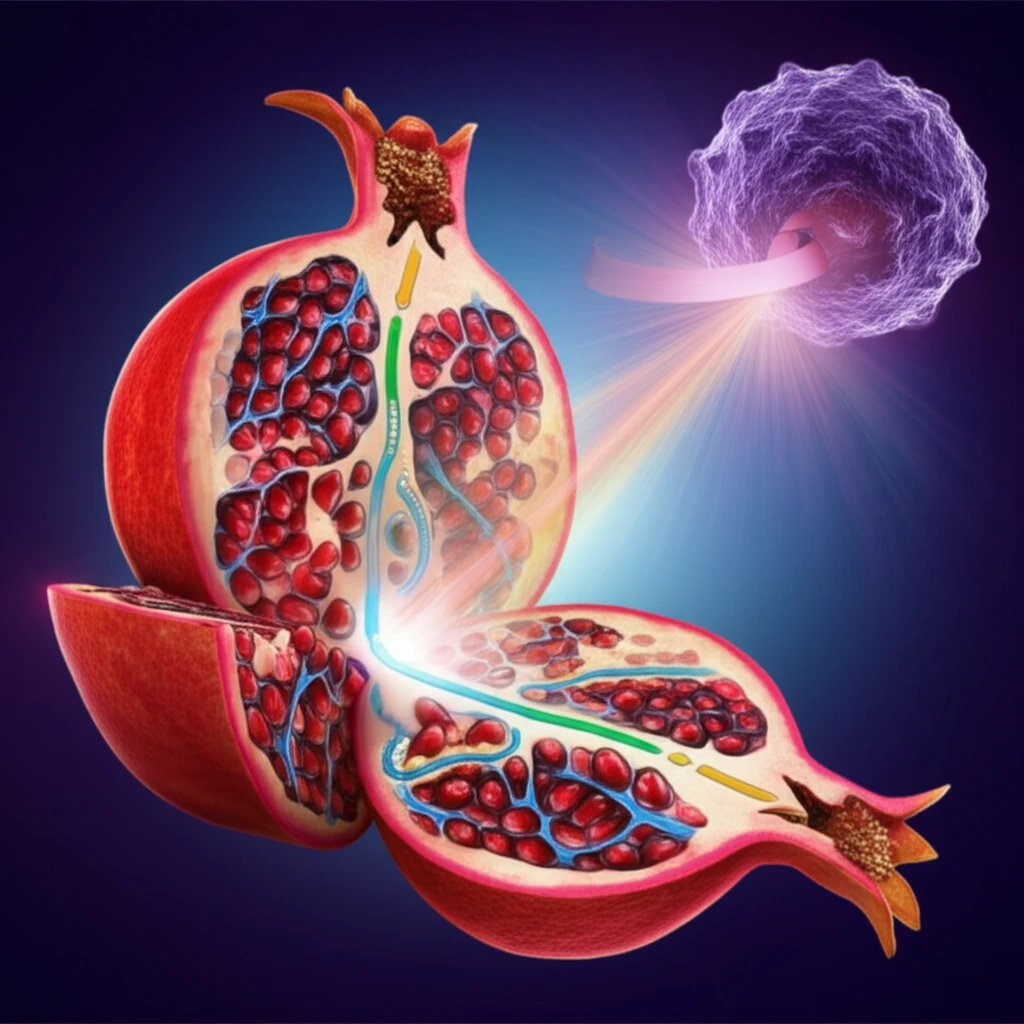

One such compound, Urolithin A (Uro A), a metabolite of ellagitannins found in pomegranates, has emerged as a promising candidate. Uro A exhibits potent antioxidant and anti-inflammatory properties, suggesting it could play a significant role in cancer prevention and treatment. Unlike its precursor, ellagic acid, Uro A is well-absorbed and tolerated, making it an attractive therapeutic option. Recent research has focused on Uro A's ability to target key signaling pathways involved in cancer development, particularly the PI3K/AKT/mTOR pathway, which is crucial for cell growth and survival. This article explores the potential of Uro A as a novel agent in the fight against pancreatic cancer, detailing its mechanisms of action and the latest findings from preclinical studies.

The PI3K/AKT/mTOR pathway is a critical regulator of cell growth, proliferation, and survival. In many cancers, this pathway is hyperactivated, driving uncontrolled cell growth and resistance to cell death. The original study highlights Urolithin A's ability to disrupt this pathway, effectively targeting the core mechanisms that fuel pancreatic cancer progression. Researchers demonstrated that Uro A could simultaneously inhibit multiple points within this pathway, preventing the cancer cells from bypassing the treatment through alternative routes.